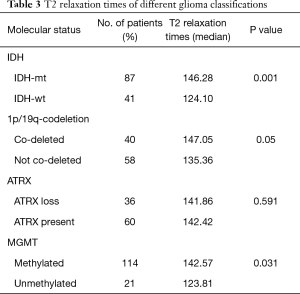

Table 3 and Figure 3 show the median T2 relaxation times and comparisons between molecular categories. The T2 relaxation time distribution was significantly different between IDH-mt and IDH-wt gliomas (P=0.001) and between MGMT-methylated and MGMT-unmethylated gliomas (P=0.03). Borderline significance was found between 1p/19q-codeleted and not co-deleted gliomas (P=0.05). No distribution difference was observed between ATRX gene loss and present gliomas; however, when T2 relaxation times were used as a diagnostic tool to predict molecular category, they could not make accurate predictions, with all AUCs were between 0.5–0.7. Table 4 shows the ROC analysis for predicting the IDH status, with an AUC of 0.687.